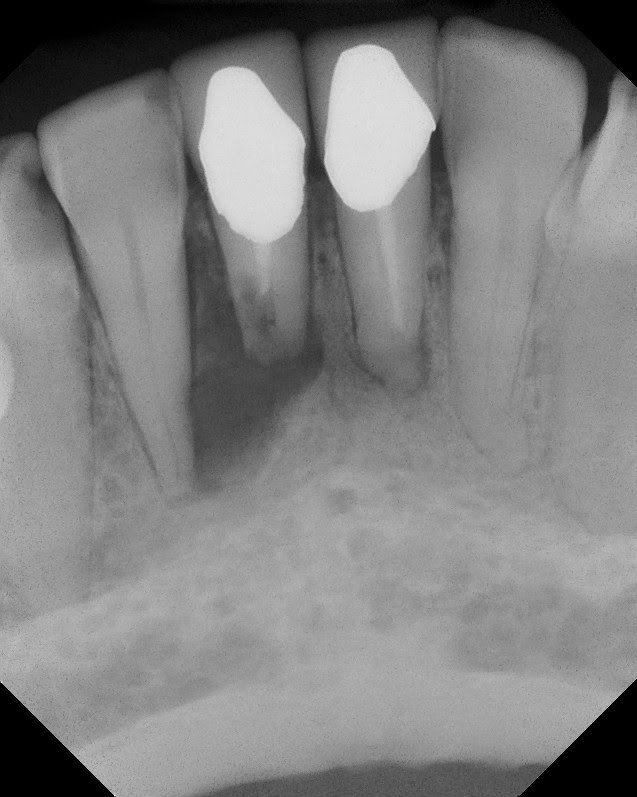

From this point, the patient has remained asymptomatic and we have seen full resolution of PARL.

This is a tooth that would be extracted by most dentist, and by many endodontists, however, apical surgery is too often overlooked as a treatment option.